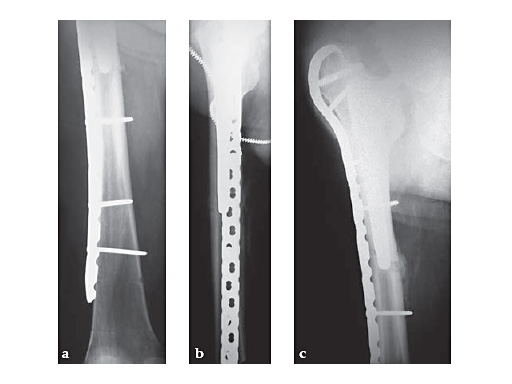

An additional important indication is periprosthetic fracture about the femoral component of a total hip arthroplasty. The trochanteric fixation of the plate (both hook and screws) affords improved proximal fixation, in many cases limiting the need for circlage wires and screws angled around the stem. Compression of primary fracture planes remains desirable in the periprosthetic setting, but is often not possible and does not limit the utility of the plate in this clinical setting. The Plate is available in lengths of 133385 mm, or 216 holes.

83-year-old maletrapped under tree he had cut downIDDM, HTN, CAD, etcJehovahs witnesson Plavix

Case provided by Keith Mayo, Tacoma, USA